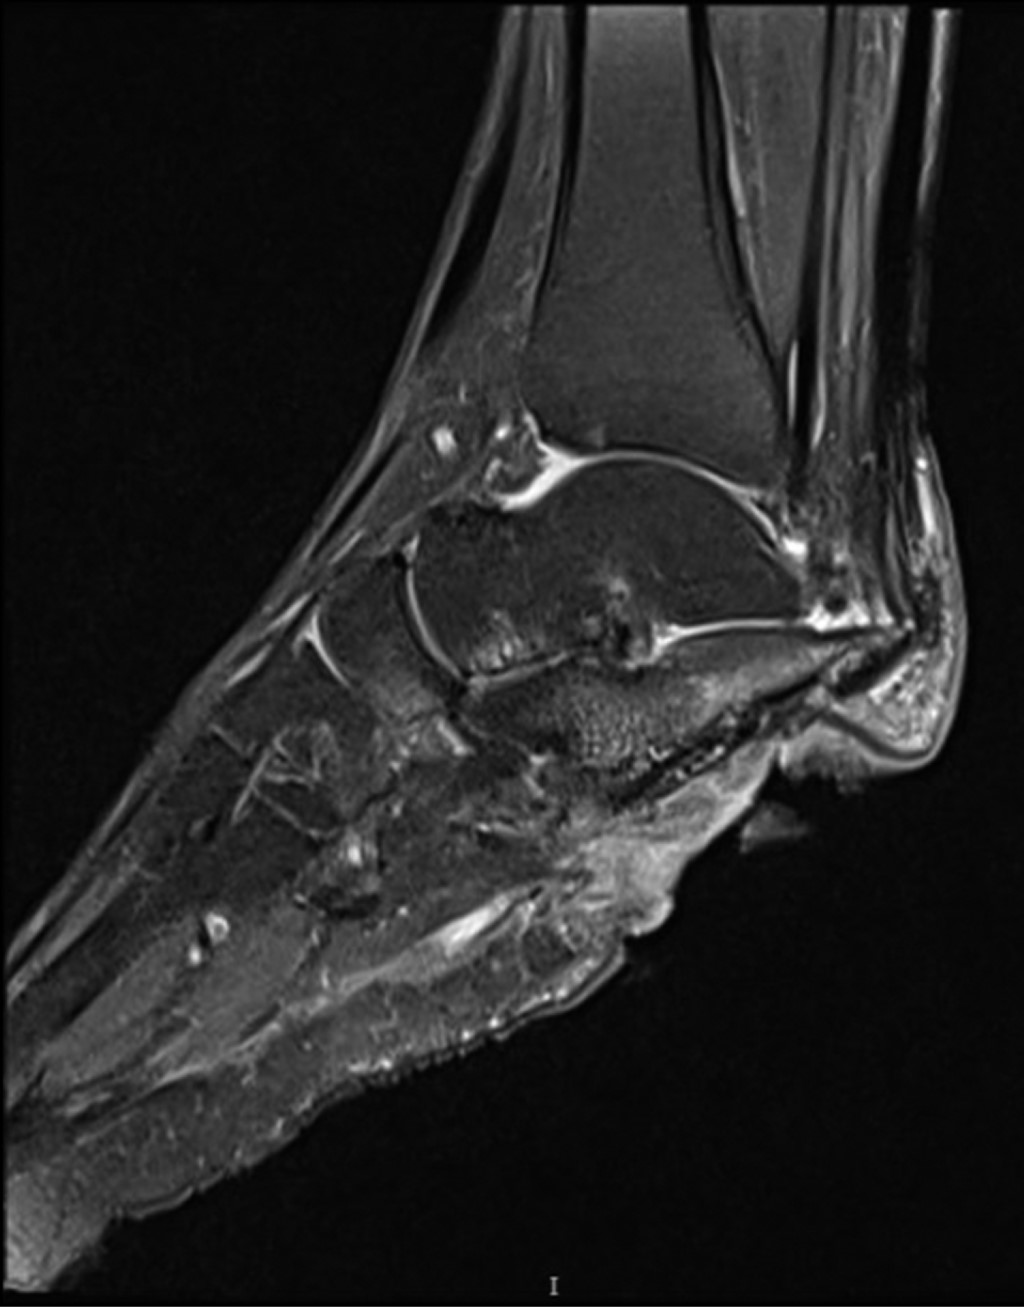

Chronic osteomyelitis of calcaneus: a case report and literature review

We present the case of a 38-year-old male patient at the Miguel Hidalgo Hospital Centenario, Aguascalientes, Mexico, with a five-year history of chronic ulcer on the right heel after direct trauma with a sharp object to the involved heel, with history of flap advancement five years ago. Clinical examination with 7 × 5 cm skin loss with purulent exudate and radiological examination revealed an image of hypotrophy of the right calcaneus with sclerosed bone remains and data suggestive of chronic osteomyelitis. After a first intervention with a polymethylmethacrylate + gentamicin cement spacer with a chain technique and calcaneal curettage, as well as taking a culture, the diagnosis was confirmed with isolation of the Escherichia coli lesion and Enterococcus faecalis, but the spacer was rejected, he intervenes again for calcaneal resection. When the wound heals, ankle foot orthosis is indicated and walking is started without pain, and without recurrence of osteomyelitis.

Figure 1